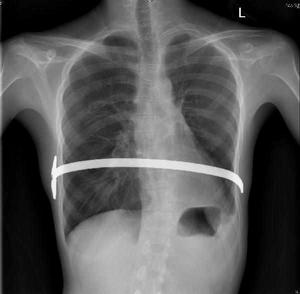

胸部X線表現:①孤立性肺囊腫。液囊腫為圓形或橢圓形,密度均勻,邊緣光滑的陰影。氣囊腫為薄壁環形陰影。張力性含氣囊腫可形成巨大的氣囊,壓迫周圍肺組織,使縱隔向對側移位。液氣囊腫可見液平面,如囊腫內有間隔形成多房,可有多個液氣平面形成。合併感染時,囊壁增厚,囊腫周圍出現炎性浸潤性陰影。②多發性肺囊腫。肺野內見很多薄壁環形透光區,大小不等,相互重疊,似蜂窩狀。有時囊腔內也可出現液氣平面。